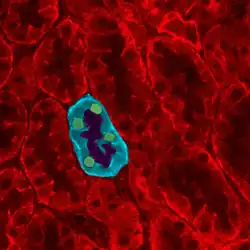

Fig.6) Cross-sectional histologic preparation showing (b)small connecting tubules with simple columnar epithelium and (a) large connecting tubules with simple cuboidal epithelium.

Each distal convoluted tubule delivers its filtrate to a system of collecting ducts, the first segment of which is the connecting tubule. The collecting duct system begins in the renal cortex and extends deep into the medulla. As the urine travels down the collecting duct system, it passes by the medullary interstitium which has a high sodium concentration as a result of the loop of Henle's countercurrent multiplier system.[1]: 67